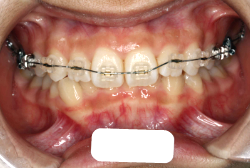

「ものがうまく噛めない」という主訴で来院したケースです。診断の結果、「骨格性反対咬合に伴う咬合不良+軽度叢生」と判明しました。原因としては特に下顎の左側が過成長したため、骨格性反対咬合になり、特に左側での噛み合わせが非常に悪くなっていると診断しました。初診時の写真を見ると、上下の正中線の大きなズレ、左側の噛み合わせの不良がはっきり分かります(黄色の矢印と緑の矢印は一致しているのが正しい状態です)。

そもそも、このような状態となっているのは骨の大きさに問題があるため生じていますので、場合によっては、「外科矯正」によって下顎の骨を外科的に縮めることで修正します。患者様が外科矯正をご希望されない場合は、従来ですと上下左右の小臼歯抜歯を行い矯正するのが普通です。

今回の患者様の場合は、「外科」も「小臼歯抜歯」も拒否されましたので、歯科矯正用アンカースクリュー(以下 アンカースクリュー)を用いて、下顎の歯列全体を後方に下げるという方法を取りました。

治療中の写真で、アンカースクリューより歯を後ろへ牽引しているのがお分かりいただけるかと思います。牽引を1年ほど続け、途中補助的に上下にゴムをかける(これを顎間ゴムと言います)手法なども追加し、全体で21ヶ月で治療を終えることが出来ました。

結局歯の本数を減らすことなく、すべてご自分の歯を残して、正しい配列と噛み合わせにすることができました。凸凹があまりひどくないため、簡単そうに見えると思いますが、このケースの初診の状態を見ると、熟練の矯正歯科医でも悩みのつきないケースです。まして、外科も出来ない、抜歯もイヤ、と言うことになると、従来の方法では治療不可能と考えられるのですが、アンカースクリューを使うことで最近は不可能が可能となってきました。